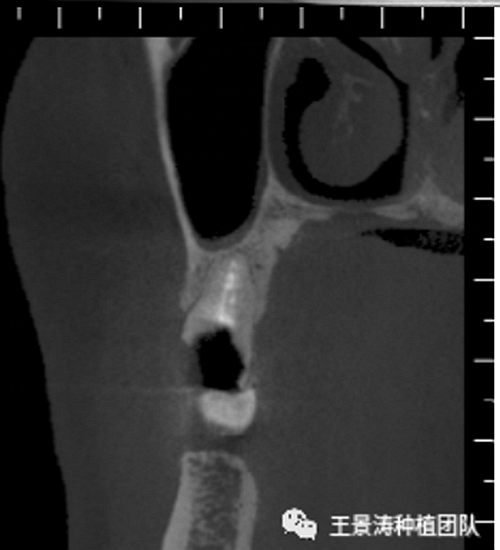

患者左側(cè)16慢性根尖周炎,17缺失。16根尖炎癥距上頜竇底較近,需內(nèi)提升,但是因?yàn)閮?nèi)提升后骨質(zhì)較薄所致植入深度過深,埋入式植入。17非埋入式種植。后期效果均可。